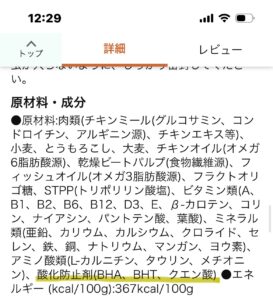

結石は 型が薄くなっているのでは?と 血尿や残尿感 膀胱炎が悪化しないように 引き続き 栄養と膀胱粘膜管理 尿の検査を頑張ってもらってます。

そらちゃん 定期的に関節に水が溜まる事と軟便が中々治らない事 に関しては 再発予防のホームケアプランを提案させてもらいます。